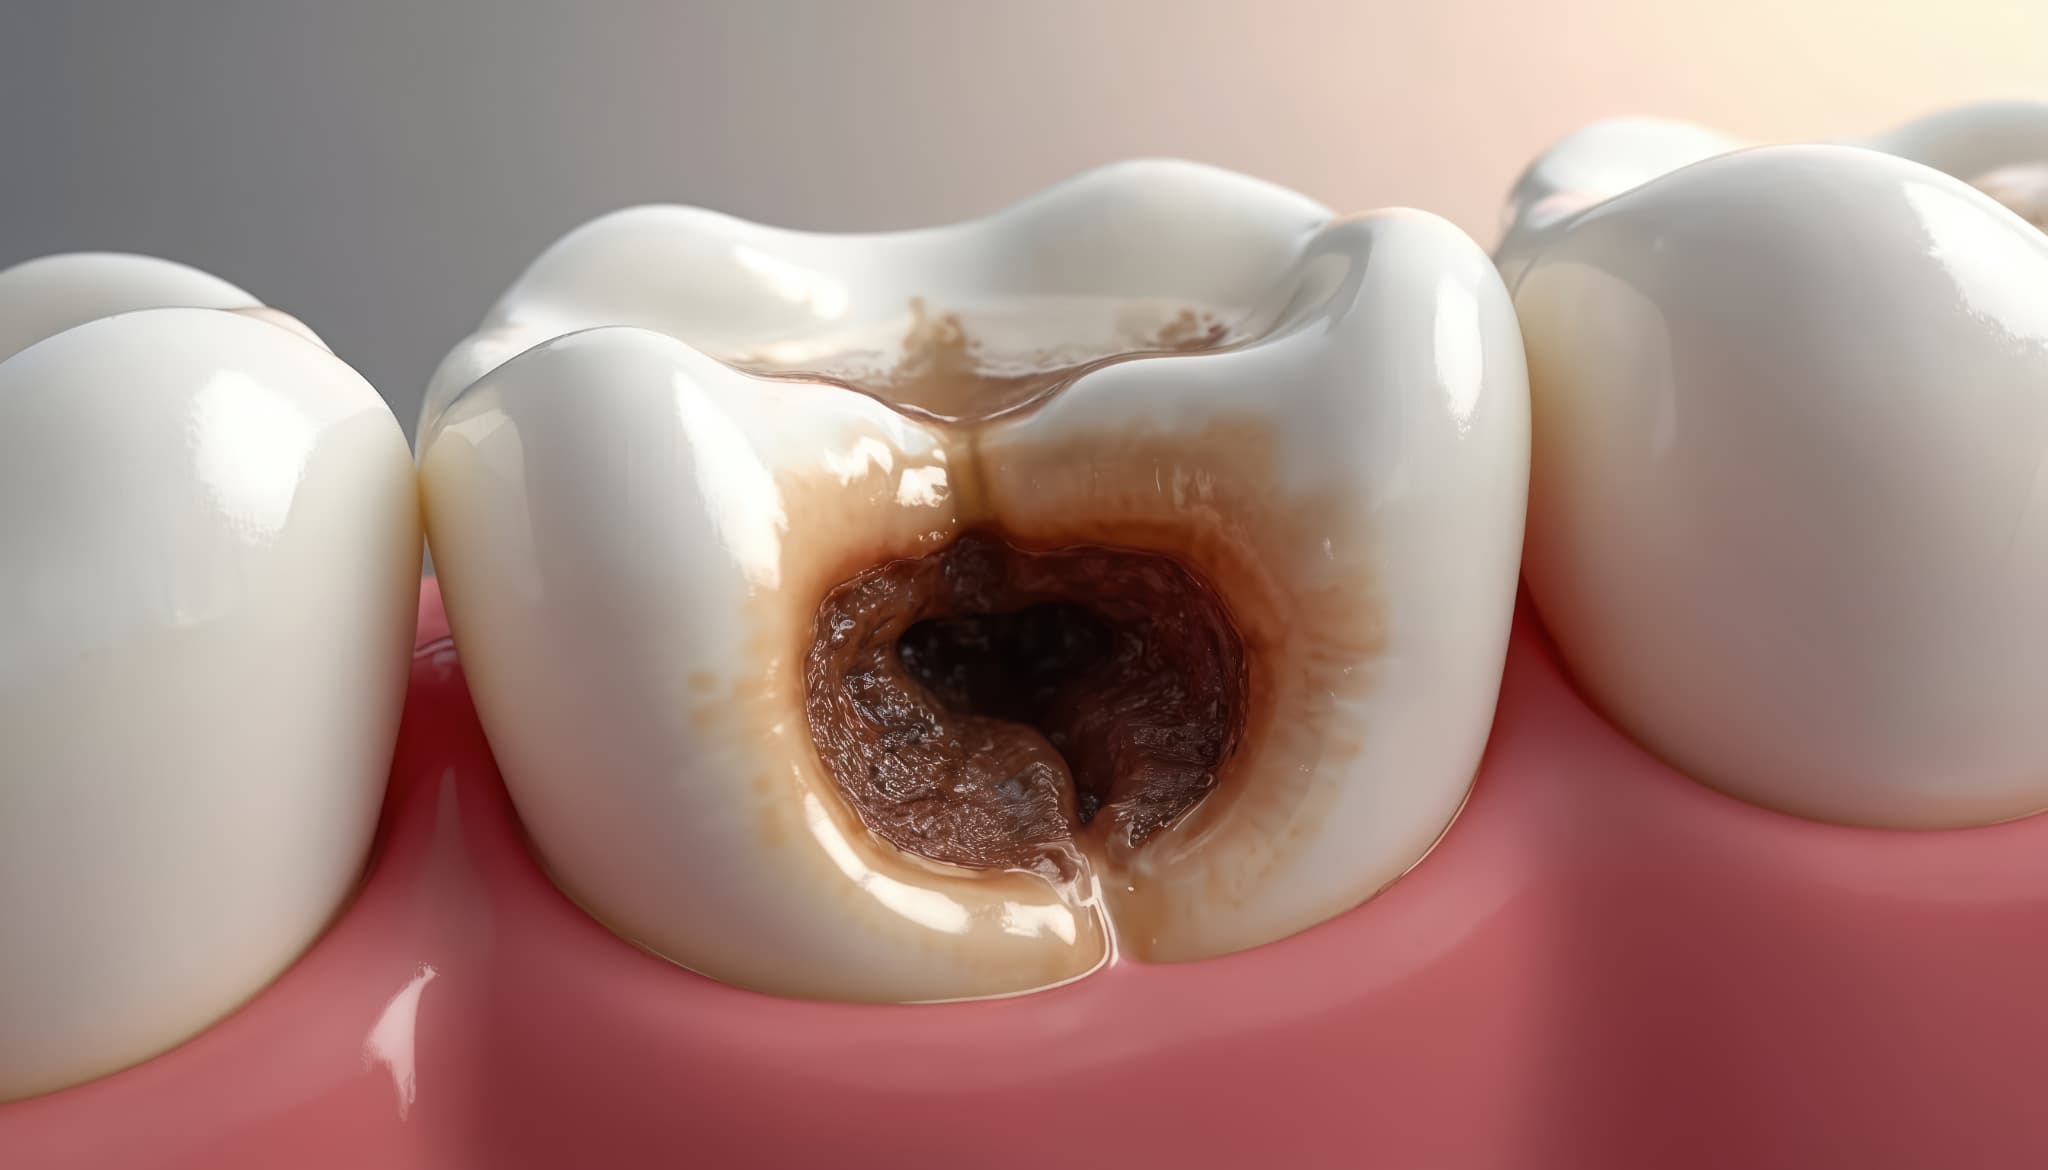

重度の虫歯とは

重度の虫歯のイメージ

重度の虫歯は、虫歯がエナメル質や象牙質を超えて歯髄(神経)まで進行し、強い痛みや腫れ、膿が出るなどの症状が現れる状態を指します。

虫歯の進行度はC1〜C4に分類され、歯髄に達したC3や歯冠が崩壊したC4は、一般的に重度の虫歯とされています。

初期の虫歯と比較して進行が著しく、放置すると歯の保存が難しくなるため、早期の治療が重要です。

重度の虫歯では、冷たいものや甘いものを口にした際の強い痛みだけでなく、何もしていなくてもズキズキとした自発痛が現れます。

歯の表面に大きな穴があき、黒ずみや歯の欠けが目立つことが多く、歯茎が腫れて膿が出る場合もあります。